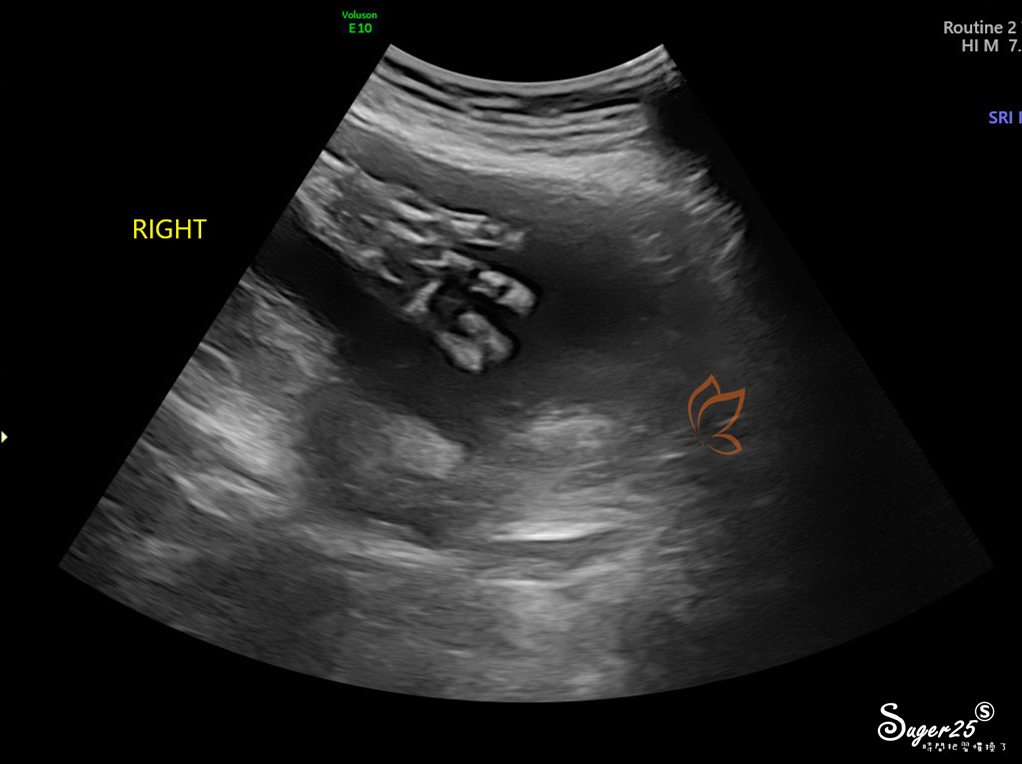

器官血液靜脈動脈之類的畫面

脊髓

手臂

大腿

手指頭

照的真的很仔細,從頭到腳,還有身體所有器官、靜脈動脈...等,左右兩邊的手跟腳